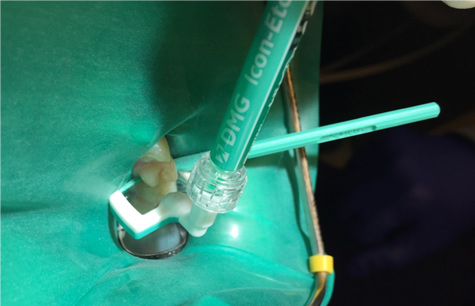

5. Insert applicator with resin infiltration material with green side and perforations facing the surface to be treated (Figure 5).

Fig 5. The proximal applicator is inserted with an etch.

Figure 5